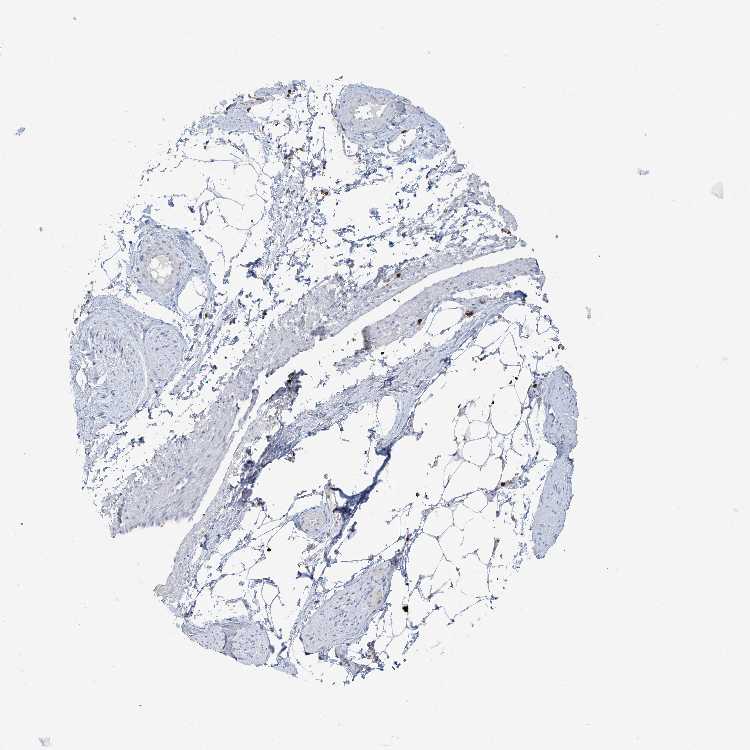

ADIPOSE TISSUE - Antibody stainingi

Antibody staining in the annotated cell types in the current human tissue is reported as not detected, low, medium, or high, based on conventional immunohistochemistry profiling in selected tissues. This score is based on the combination of the staining intensity and fraction of stained cells.

Each image is clickable and will lead to virtual microscopy that enables deeper exploration of all samples and also displays staining intensity scores, fraction scores and subcellular localization as well as patient and tissue information for each sample.

Antibody HPA035639

Adipocytes Not detected